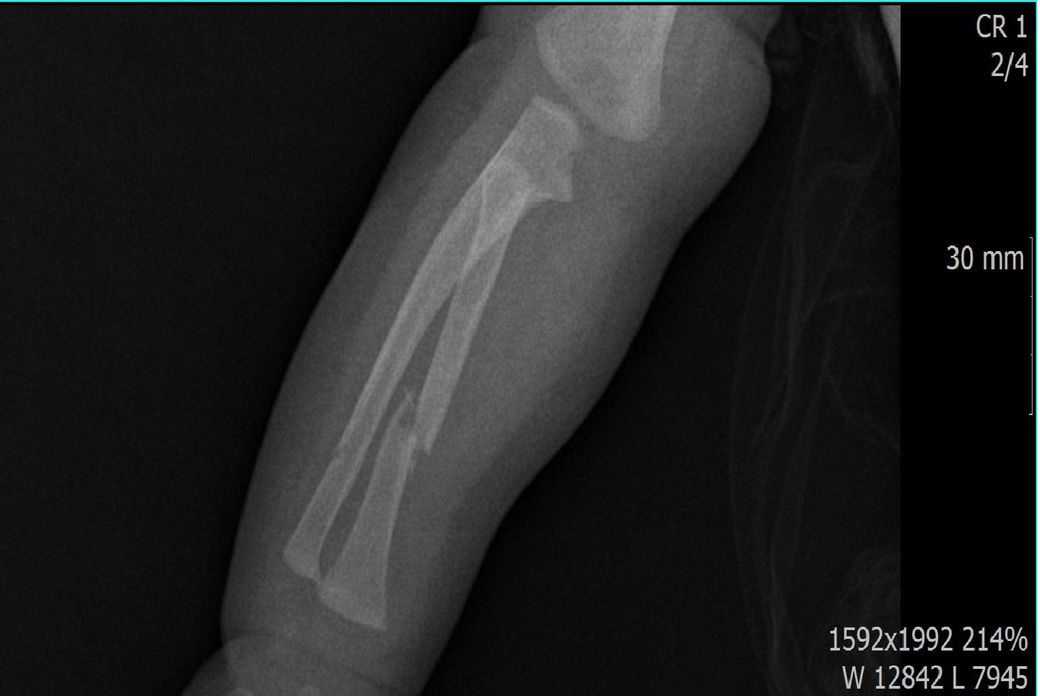

x ray 팔 골절 시기 추정해보고 싶습니다

다름이 아니라, 첨부드린 엑스레이(X-ray) 사진처럼 골절 사실을 알게 되고 골절 발생 시점 대략적으로나마 추정시기를 파악하려고 문의 드리게 되었습니다

1) 3월 30일 촬영한 X-ray만으로 정확한 골절 시기를 100% 특정하는 데에는 한계가 있다는 점 충분히 인지하고 있기에 촬영날짜 기준으로 대략적으로 어느정도 시점에서 발생되었을 것으로 추측(ex 당일, 7~10일전, 7~14일 전, 10일 ~ 20일전, 14일 ~ 30일전 등등등)되는지 이해하고 싶습니다.

첨부드린 파일에는 없지만 4월 5일 사진에서는 캘로스 라는 것이 발견된다고 합니다.

1) 하지만 촬영한 사진을 기준으로 골절시기를 며칠, 몇주 정도로 좁히는 것은 가능한 일이 아닙니다. 아마도 몇 개월간격으로는 가능할 것입니다. 보호자분이 원하시는 정보를 확인하기 위해서는 serial 한 사진, 그러니까 며칠 혹은 1-2주 간격으로 연달아 찍은 사진이 연속적으로 있어야 합니다. 그리고 그걸 보고서 판단을 합니다. 어느 한 시점의 사진만을 보고 골절시기를 추정하는 것은 가능하지 않습니다.